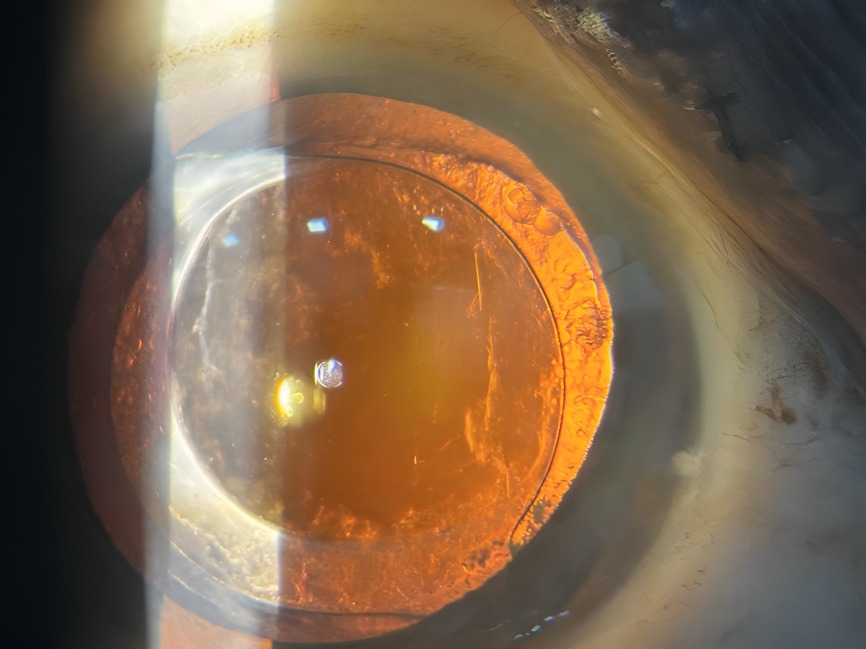

Chalazion – Successful Surgical Management At Vivaan ENT & Eye Clinic, we regularly manage eyelid conditions such as chalazion with safe, effective, and minimally invasive procedures. Recently, a patient underwent chalazion incision and curettage, performed by Dr. Veena Karkhele (Garje) under local anesthesia. The procedure was completed smoothly, and the patient had an excellent post-operative recovery with significant relief from swelling and discomfort.